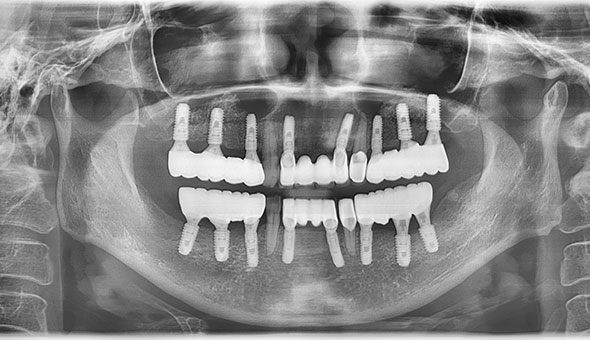

네비게이션 임플란트는 길을 알려주는 네비게이션처럼 치조골의 구조와 신경 위치를 파악하여 정확하게 임플란트를 식립할 수 있는 임플란트 방법을 말합니다.

네비게이션 임플란트는 3D CT를 통해 입체 영상으로 정확한 수술 계획을 세우고, CT자료를 기반으로 구강에 끼우는 보조장치를 제작하여 잇몸 절개없이 작은 구멍을 뚫어 임플란트를 식립하여, 잇몸을 절개하는 수술방법보다 통증과 출혈이 적어 비교적 회복이 빠르게 나타납니다.

네비게이션 임플란트는 3D CT를 통해 입체 영상으로 정확한 수술 계획을 세우고, CT자료를 기반으로 구강에 끼우는 보조장치를 제작하여 잇몸 절개없이 작은 구멍을 뚫어 임플란트를 식립하여, 잇몸을 절개하는 수술방법보다 통증과 출혈이 적어 비교적 회복이 빠르게 나타납니다.